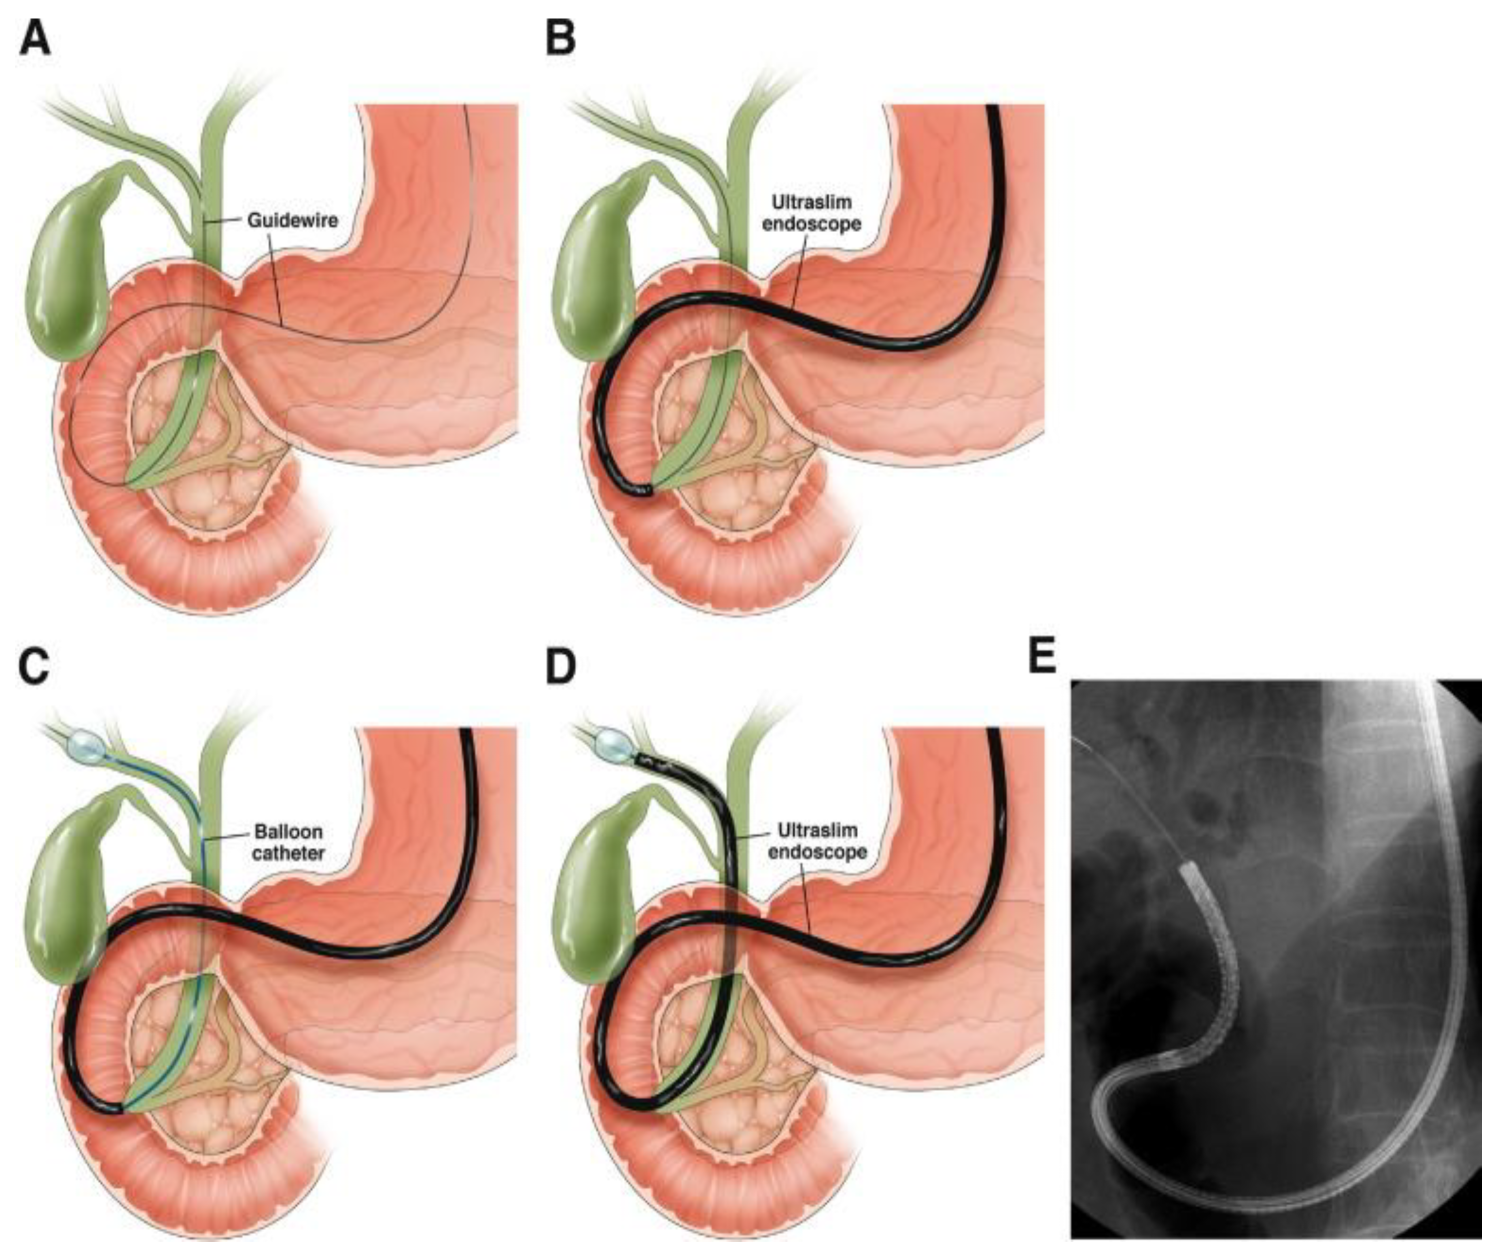

| Direct Cholangioscopy (DC) | Direct access using ultra-slim endoscope | High-definition imaging, potential for virtual chromoendoscopy | Technically challenging, potential severe adverse events |